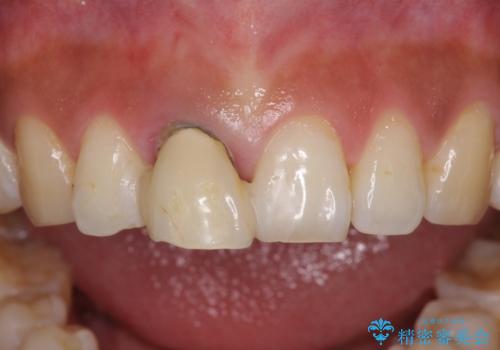

折れているのに応急処置でごまかしてきた前歯 オールセラミックブリッジによる補綴治療

- 歯根が破折しているにもかかわらず、抜歯を避けてきたため痛みが発現したとのことで来院された患者様です。

歯根破折した歯は抜歯適用となるため、速やかに抜歯を行い、傷が治り次第オールセラミックブリッジにて補綴治療を行うこととしました。